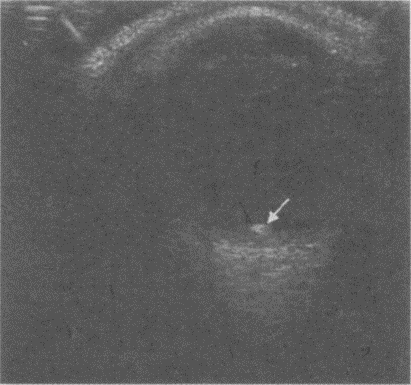

200、单项选择题

患者,女,14岁,眼部外伤两小时。超声检查如图,最可能的诊断为()。

A.玻璃体积血

B.玻璃体混淆

C.脉络膜脱离

D.视网膜脱离

E.以上均不是